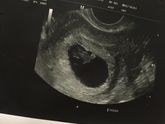

Эх, кошмары зачастили и нервы ни к черту. Плачу из-за всего: из-за котика бездомного под окном, из-за прыщей на лице (повылазили, заразы!), из-за того, что токсикозит, из-за того, что НЕ токсикозит (а вдруг замершая!!!) и смех, и грех, и пытаюсь себя … Читать далее